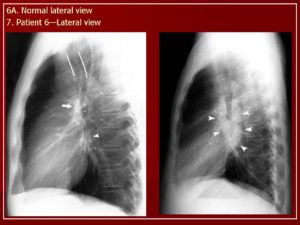

Корень легкого выглядит как затемнение на фоне легочной ткани. Его можно обнаружить на границе легких и средостения на уровне I-IV ребра.

На рентгене большую часть тени корня создают артерии, поскольку они имеют большую плотность по сравнению с другими элементами. Бронхи содержат воздух, потому их различают по полоскам просветления на фоне сосудистого рисунка.

Расширение

В норме ширина корня легкого соответствует ширине его артериального компонента и в области тела корня равняется 15 мм. Как правило, корни легкого расширяются с обеих сторон, но правый измерить легче, чем левый. Из-за того, что структуры левого легкого на рентгеновском снимке частично прикрыты тенью сердца, левосторонняя патология обнаруживается позднее.

Часто корни легких расширены вследствие увеличения их сосудистого компонента. Это наблюдается при левожелудочковой сердечной недостаточности, когда повышается давление в легочных венах из-за застоя в них крови. В легочной артерии давление может повышаться при заболеваниях легких, например, эмфиземе или ателектазе.

После описания легочных полей следует анализ корней легких. Нормальное их состояние – не расширены, структурны. В каждом корне на рентгеновском снимке можно выделить головку, тело и хвост.

Если четко выявить такие анатомические образования не представляется возможным, расшифровка изменяется – «корни не структурны».